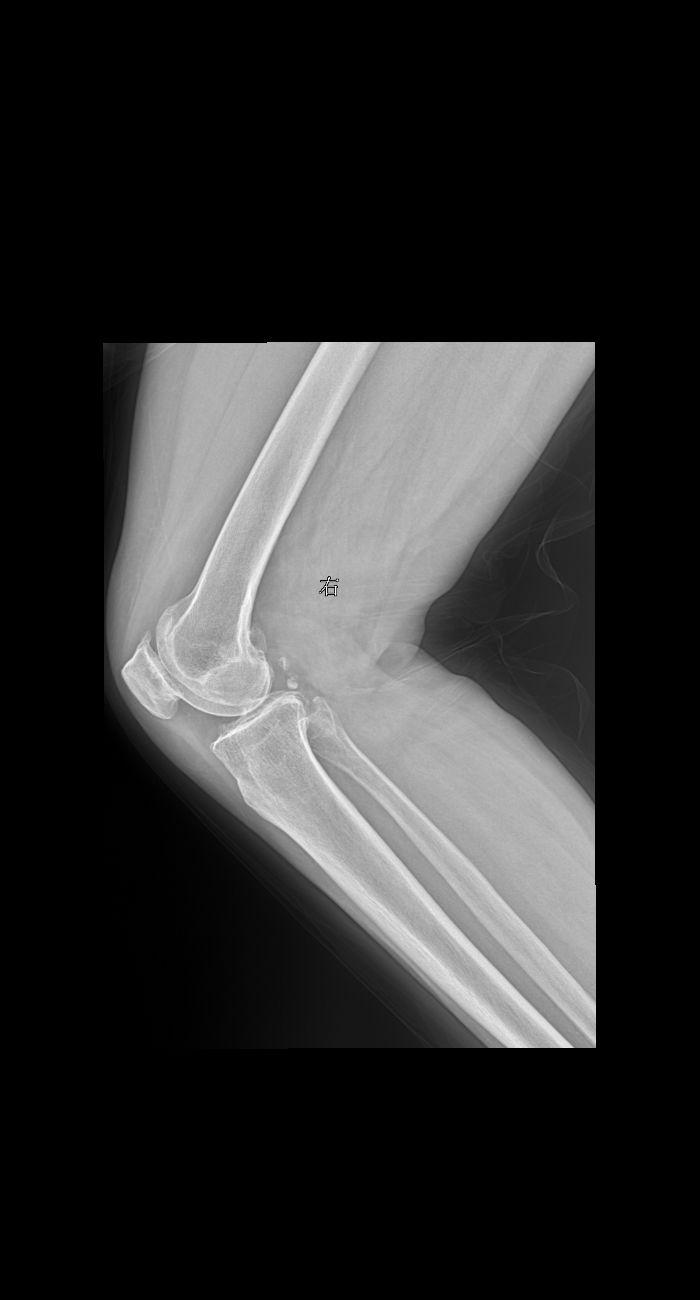

患者女 74岁行走时膝关节疼痛就诊